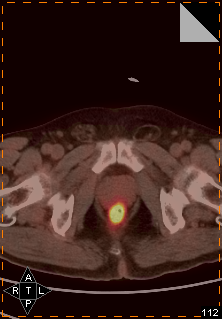

PET/CT示:

直肠壁增厚,伴局灶性FDG代谢异常增高,考虑恶性病变可能大,建议肠镜检查